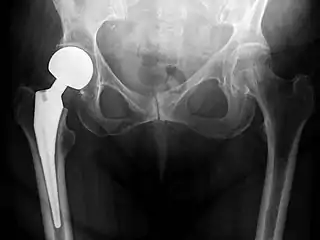

Post-operative projectional radiography is routinely performed to ensure proper configuration of hip prostheses.

Hip replacement is a surgical procedure in which the hip joint is replaced by a prosthetic implant, that is, a hip prosthesis. Hip replacement surgery can be performed as a total replacement or a hemi (half) replacement. Such joint replacement orthopaedic surgery is generally conducted to relieve arthritis pain or in some hip fractures. A total hip replacement (total hip arthroplasty or THA) consists of replacing both the acetabulum and the femoral head while hemiarthroplasty generally only replaces the femoral head. Hip replacement is one of the most common orthopaedic operations, though patient satisfaction varies widely. Approximately 58% of total hip replacements are estimated to last 25 years.[1] The average cost of a total hip replacement in 2012 was $40,364 in the United States, and about $7,700 to $12,000 in most European countries.[2]